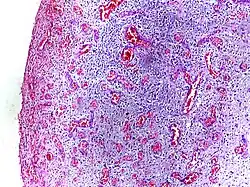

Micrograph showing granulation tissue. H&E stain.